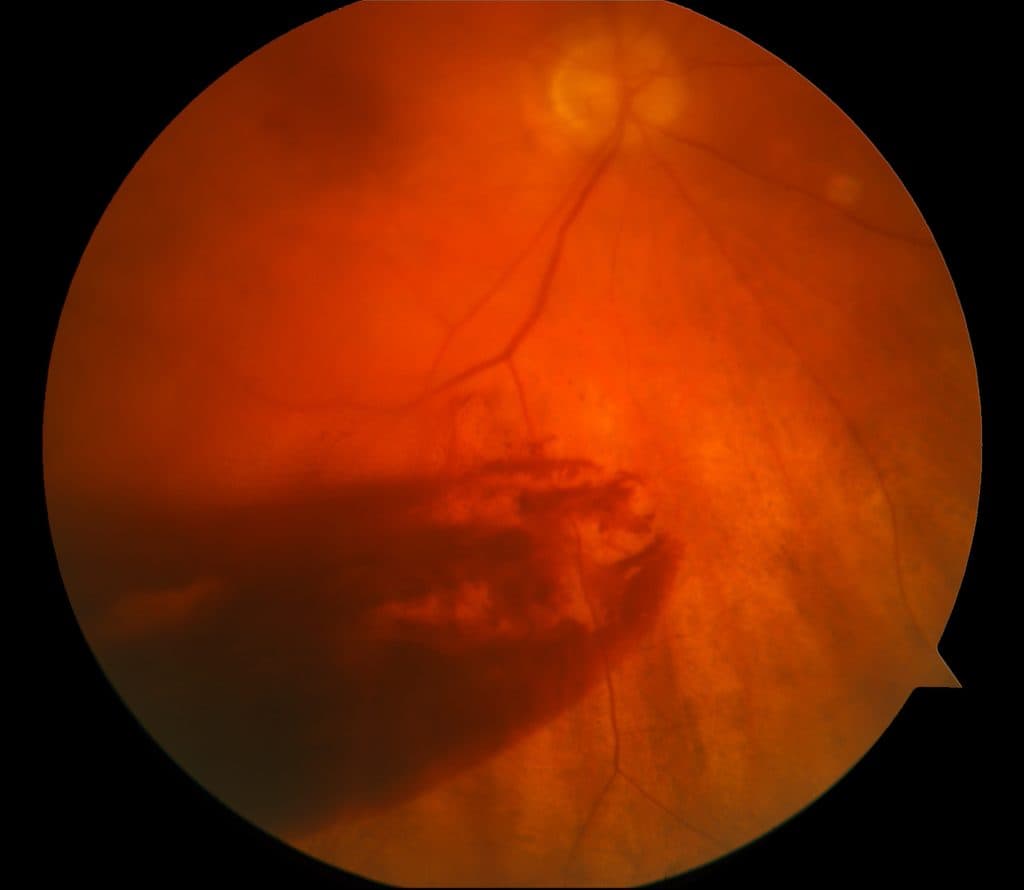

Xuất huyết dịch kính là tình trạng máu tràn vào khoang dịch kính, một khu vực chứa chất gel trong suốt nằm giữa thủy tinh thể và võng mạc. Dịch kính đóng vai trò quan trọng trong việc duy trì cấu trúc của mắt và hỗ trợ ánh sáng đi qua để tạo hình ảnh trên võng mạc. Khi xảy ra chấn thương, các mạch máu trong mắt, đặc biệt là ở võng mạc hoặc các cấu trúc lân cận, có thể bị vỡ, gây ra hiện tượng xuất huyết. Máu tích tụ trong dịch kính làm cản trở ánh sáng, dẫn đến giảm thị lực hoặc nhìn mờ.

Triệu chứng của xuất huyết dịch kính sau chấn thương thường xuất hiện ngay sau khi xảy ra va chạm, mặc dù ở một số trường hợp, các dấu hiệu có thể xuất hiện muộn hơn. Một trong những triệu chứng phổ biến nhất là giảm thị lực đột ngột hoặc nhìn mờ, giống như có một lớp sương mù che phủ trước mắt. Người bệnh cũng có thể thấy các đốm đen, vệt sáng, hoặc các hình dạng trôi nổi trong tầm nhìn, thường được gọi là “ruồi bay”.

Ngoài ra, một số người có thể cảm nhận được áp lực hoặc đau nhẹ trong mắt, đặc biệt nếu chấn thương gây tổn thương các cấu trúc khác như giác mạc hoặc mống mắt. Trong các trường hợp nghiêm trọng, người bệnh có thể mất hoàn toàn thị lực ở mắt bị ảnh hưởng hoặc cảm thấy nhạy cảm với ánh sáng. Những triệu chứng này có thể trở nên nghiêm trọng hơn nếu không được điều trị kịp thời, dẫn đến nguy cơ tổn thương võng mạc hoặc tăng nhãn áp.